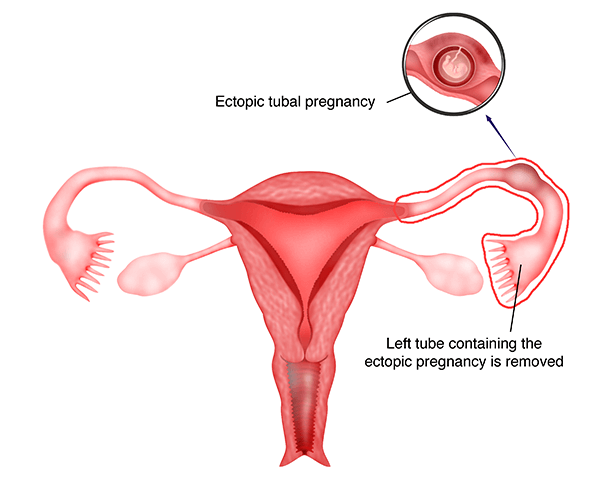

1) Salpingektomi Laparoskopi

Teknik ini meliputi eksisi tuba yang berisi kehamilan ektopik. Eksisi dapat dilakukan dengan menggunakan teknik 3 atau 4 port atau dengan teknik sayatan tunggal. Pada teknik 3 atau 4 port, tuba di tahan dengan grasper dan mesosalping ( jaringan yang menahan tuba ke rahim ) dikoagulasikan dengan menggunakan aliran bipolar, dan kemudian dipotong. Tuba yang berisi kehamilan ektopik kemudian terlepas dari rahim dan ovarium.

Tindakan perawatan harus dilakukan sedekat mungkin dengan tuba karena terkadang pembekuan yang berlebihan dapat menyebabkan suplai darah ke ovarium terganggu. Pada ruptur kehamilan ektopik, mungkin ada perdarahan aktif dan perdarahan ini terlebih dahulu harus dikoagulasi sebelum mencoba mengeluarkan tuba. Darah dan gumpalan darah yang muncul di rongga perut dan panggul harus segera disedot dan terkadang bisa menjadi masalah yang membosankan.

Jaringan ektopik kemudian ditempatkan kedalam kantong dan diangkat melalui panggul. Irigasi yang berlebihan pada panggul dan perut dilakukan untuk mengangkat semua darah yang telah terakumulasi di panggul.

Keunggulan dari salpingektomi laparoskopi adalah tuba dengan kehamilan ektopik dapat diangkat dan oleh karena itu tidak akan ada kekhawatiran mengenai beberapa jaringan kehamilan ektopik yang tersisa di panggul.

Kerugiannya adalah pengangkatan tuba dapat mengurangi kehamilan spontan. Apabila tuba yang lainnya paten, pasien masih memiliki kemungkinan untuk kehamilan spontan. Akan tetapi, jika tuba tersumbat / terblokir atau rusak, dia hanya akan bisa hamil melalui fertilisasi in vitro

( IVF ).